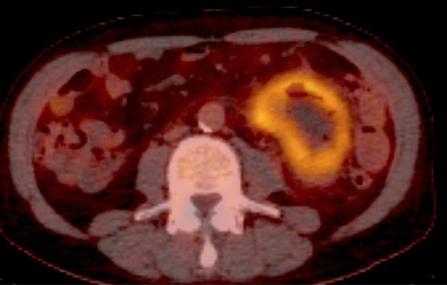

Meme cas en PET /CT . Coupe

axiale . |